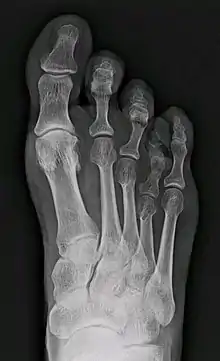

X-ray of congenital brachymetatarsia involving fourth metatarsal bone | |

It most frequently involves the fourth metatarsal. If it involves the first metatarsal, the condition is known as Morton's syndrome. Treatment is via a number of differing surgical procedures.[3]